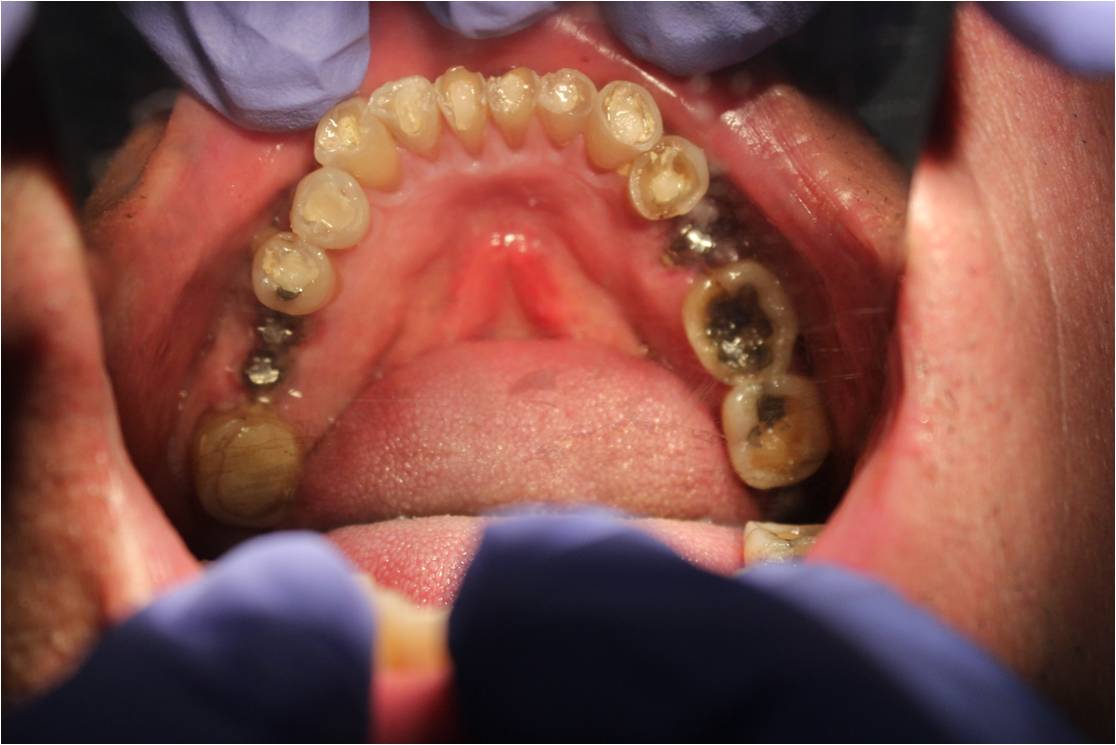

OCCLUSAL VIEW OF UPPER JAW WITH SEVERE ATTRITION ,DENTAL CARIES AND MISSING TEETH

OCCLUSAL VIEW OF LOWER JAW WITH SEVERE

ATTRITION